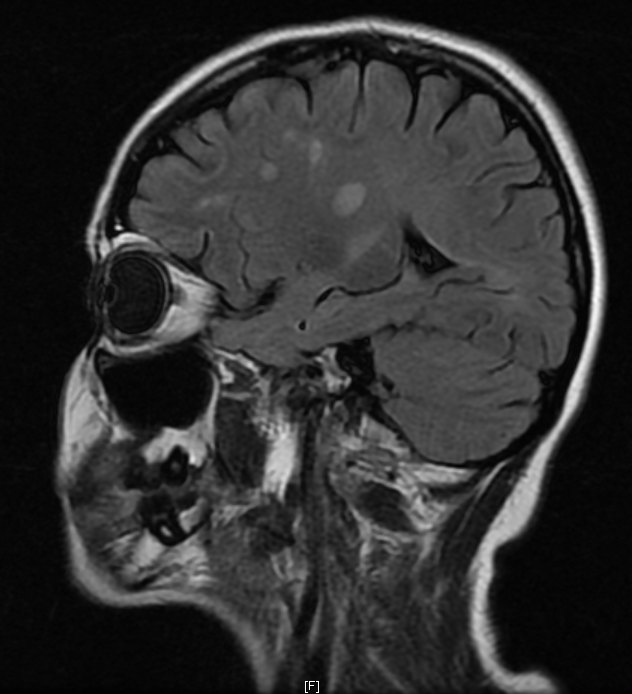

Objetivo: Relatar o caso de recidiva de herpes-zoster (HZ) em paciente com esclerose múltipla (EM) em uso de tratamento imunomodulador (natalizumabe) com evolução favorável. Descrição de caso: Mulher de 39 anos com diagnóstico de EM há 1 ano e 6 meses, previamente tratada com interferon 1a, começou tratamento com natalizumabe, desenvolvendo HZ após três meses de tratamento. HZ foi tratado com aciclovir, por sete dias, via oral. Seguimento ambulatorial após três meses de tratamento mostrou resolução completa das lesões, sem desencadeamento de neuralgia pós-herpética. Conclusões: As novas terapias para a EM podem estar relacionadas a diferentes tipos de efeitos adversos. Nem todos os casos de HZ, associados com novas terapias para EM, evoluem de forma desfavorável. Estudos são necessários para reconhecer os fatores de riscos para as formas graves de HZ em tais pacientes.